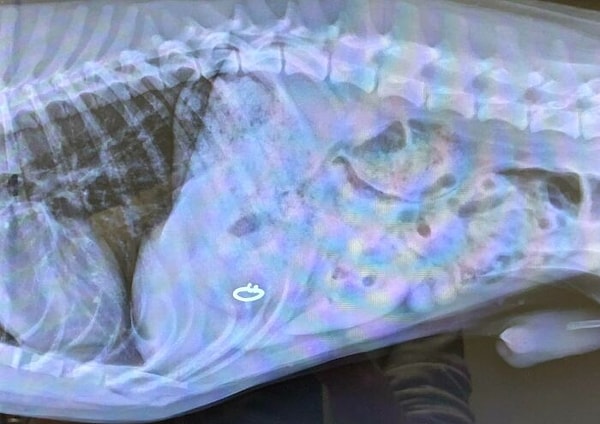

27. «Вот куда пропало обручальное кольцо жены»